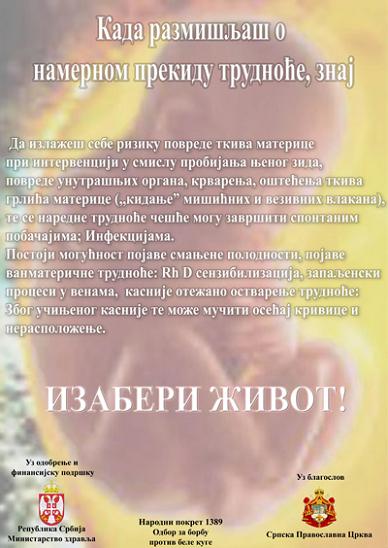

летак одбора за белу кугу, лице и полеђина летка:

радна верзија постера за здравствене установе:

Један плакат кампање - улаз

На теби је одлука. Изабери живот, не чини абортус. - погледајте